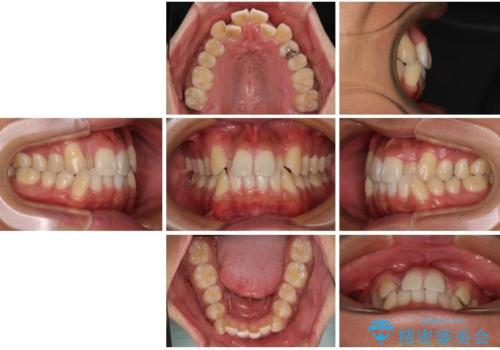

- 「八重歯を治したい」とご相談いただいた患者様の症例をご紹介します。

上下の前歯部に強い叢生(ガタガタの歯並び)があり、そのまま歯を並べると出っ歯になってしまう可能性がありました。

そこで、上下左右の第一小臼歯を抜歯し、歯が並ぶためのスペースを確保し叢生を解消する治療計画を立てました。

矯正装置は、審美性と費用面のバランスを考慮して、プラスチックブラケットとメタルワイヤーを使用しました。

透明感のあるブラケットを用いたため、従来の金属装置よりも目立ちにくく、日常生活での見た目の不安も軽減できます。